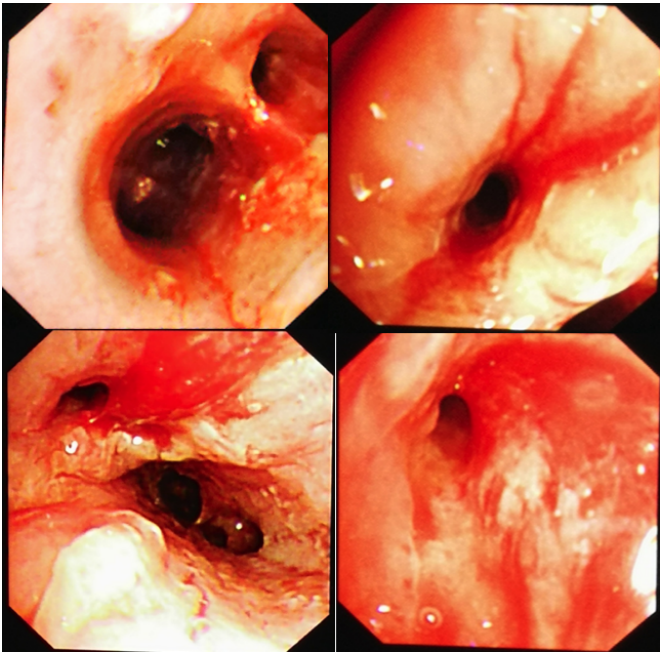

相关文献报道很少,涉及8例流感病毒相关毛霉病(IAM)和7例新型冠状病毒相关毛霉病(CAM)。笔者总结了这些患者的临床特点:①平均年龄为55岁,所以IAM/CAM可能与高龄无关;②男性发病居多,占73.3%,其中IAM发病率为62.5%,CAM发病率为85.7%;③存在至少一种除病毒感染外的基础病;④严重程度(重度);⑤危险因素:糖皮质激素,粒缺,高血糖;⑥毛霉病类型:IAM(肺毛霉病),CAM(鼻-眶-脑型毛霉病);⑦毛霉病诊断距病毒性肺炎时间:平均16.3天,偏晚。IAM/CAM的影像学相对特异,包括反晕征、厚壁空洞、大片实变伴支气管截断征(毛霉多导致支气管截断、破坏,曲霉多为支气管壁增厚、狭窄)等(图8,图9)。此外,增强CT/CT肺动脉造影(CTPA)对于毛霉病的诊断也非常重要,尤其是诊断假性动脉瘤—真菌性血管瘤,以及发现血管受侵(毛霉多侵犯大中血管)(图10,图11)。在上述15例患者IAM/CAM患者中,手术比例达到50%,大多采用了单药或联合抗真菌治疗,但病死率仍然高达66.7%,IAM病死率为37.5%,CAM患者病死率甚至达到100%。(1)危险因素:高龄可能并非病毒合并毛霉病的高危因素(平均55.7岁);男性发病更常见(73.3%);糖尿病、酸中毒、糖皮质激素是其危险因素。